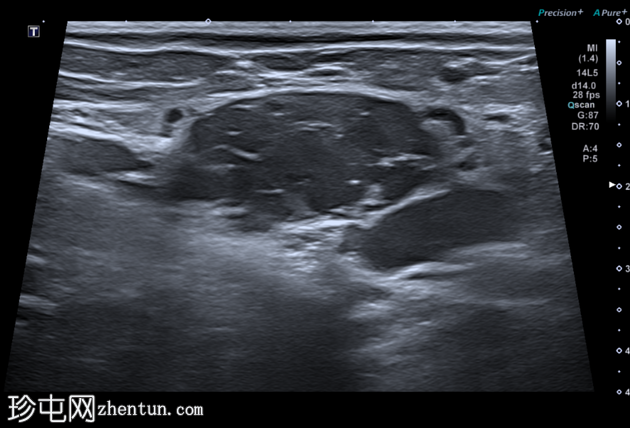

横切面

超声显示一个卵圆形低回声肿块,内部有多处分隔,与腹膜内脂肪不符,且未见蠕动(提示肠袢疝出)。

B超显示该结构内血流缓慢。